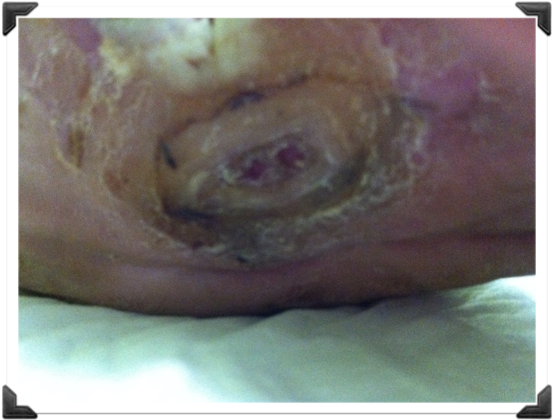

Ulcera Neuropatica

3 semanas de Post-Operatorio